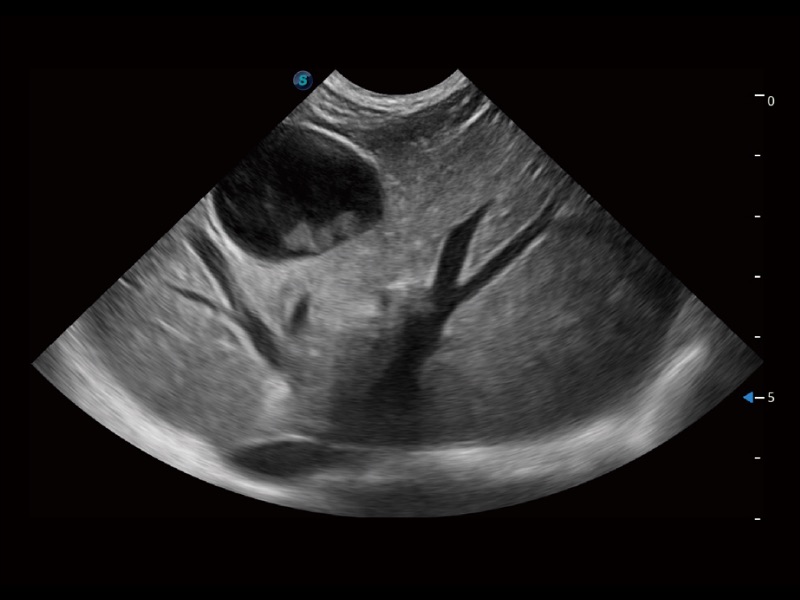

(犬)肾脏显微血流

(猫)胆囊

(猫)肺动脉血流频谱

(犬)左室长轴血流

(犬)髂动脉血流

(犬)四腔心

(犬)胎儿主动脉弓立体血流

(犬)肝脏

(犬)四腔心MQA